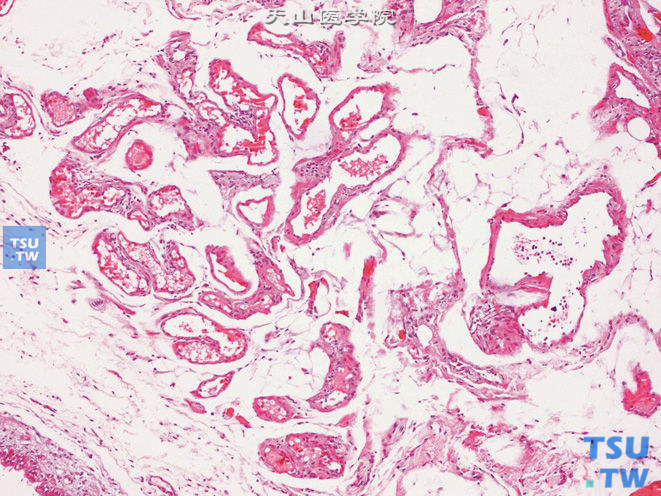

• 精索静脉曲张病理图谱

CT,精索静脉曲张,男,48岁,阴囊坠胀感。右侧阴囊见纡曲管状T1WI稍高T2WI稍低信号灶,DWI未见异常信号精索静脉曲张。示精索静脉因纡曲而呈结节状精索静脉曲张。示纡曲的静脉腔内